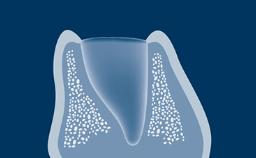

When providing a patient with an implant-supported rehabilitation, clinicians must decide whether to fabricate a provisional prosthesis or go directly to the definitive prosthesis.

Several factors play a role in making the correct decision. These involve the location of the implant anterior or posterior site, the number of implants, the need to shape tissue, as is often seen with adjacent implants in the anterior area, and the need for occlusal support.